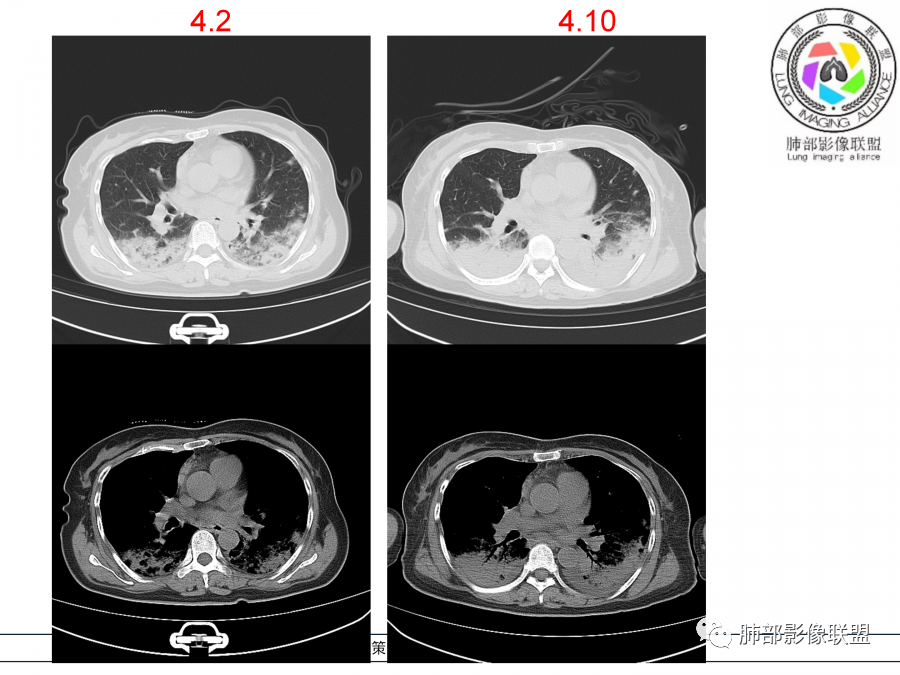

影像,第一次双肺中下叶胸膜下多发斑片状实变影,部分融合成,周围散发磨玻璃影,磨玻璃影内可见小叶间隔及小叶内间隔增厚,病变平行于胸膜,第二次间隔8天,双肺实变影明显进展,有重力作用,支气管近端堵塞,进展较快,临床有发热,血沉高,狼疮SLE阳性,考虑1:OP(机化性肺炎)2:SLE相关肺炎,建议支气管镜灌洗液病原学检测。

老年女性,咳嗽咳痰伴发热7天,白细胞不高,血沉快,降钙素原不高。其他化验未见明显异常,狼疮全套抗Ro/SSA阳性,双肺野靠近胸膜下磨玻璃实变影,支气管通畅,有充气征,沿胸膜下分布,有细网格征,7天后进展明显,实变影加重,胸膜肥厚,胸水不明显,心包少量积液?抗感染治疗无效,考虑非感染性疾病可能性大,结缔组织相关性肺病?狼疮性肺炎?机化性肺炎?鉴别病毒性肺炎。

老年女性,咳嗽咳痰发热7天。无气促。白细胞计数不高,PCT稍高,PPD(+),抗Ro/SSA阳性。CT:双肺野靠近胸膜下磨玻璃实变影,支气管通畅,有充气征,沿胸膜下分布,有细网格征。予抗生素治疗,8天后复查胸部CT见病灶范围扩大,实变影加重,胸膜肥厚,胸水不明显。抗感染治疗无效,考虑有:1.非感染性疾病:结缔组织相关性肺病,支持点:肺部CT表现为间质性炎症病变,抗RO/SSA(52)阳性;2.病毒性肺炎:患者无气促症状,可能性小;3.肺结核。

第一次双肺中下叶胸膜下多发斑片状磨玻璃及实变影,病变平行于胸膜,支气管通畅,8天后,双肺实变影明显进展范围扩大,部分支气管近端堵塞,进展较快,胸腔积液,抗感染治疗无效,考虑:非感染性疾病:结缔组织相关性肺病。鉴别机化性肺炎。